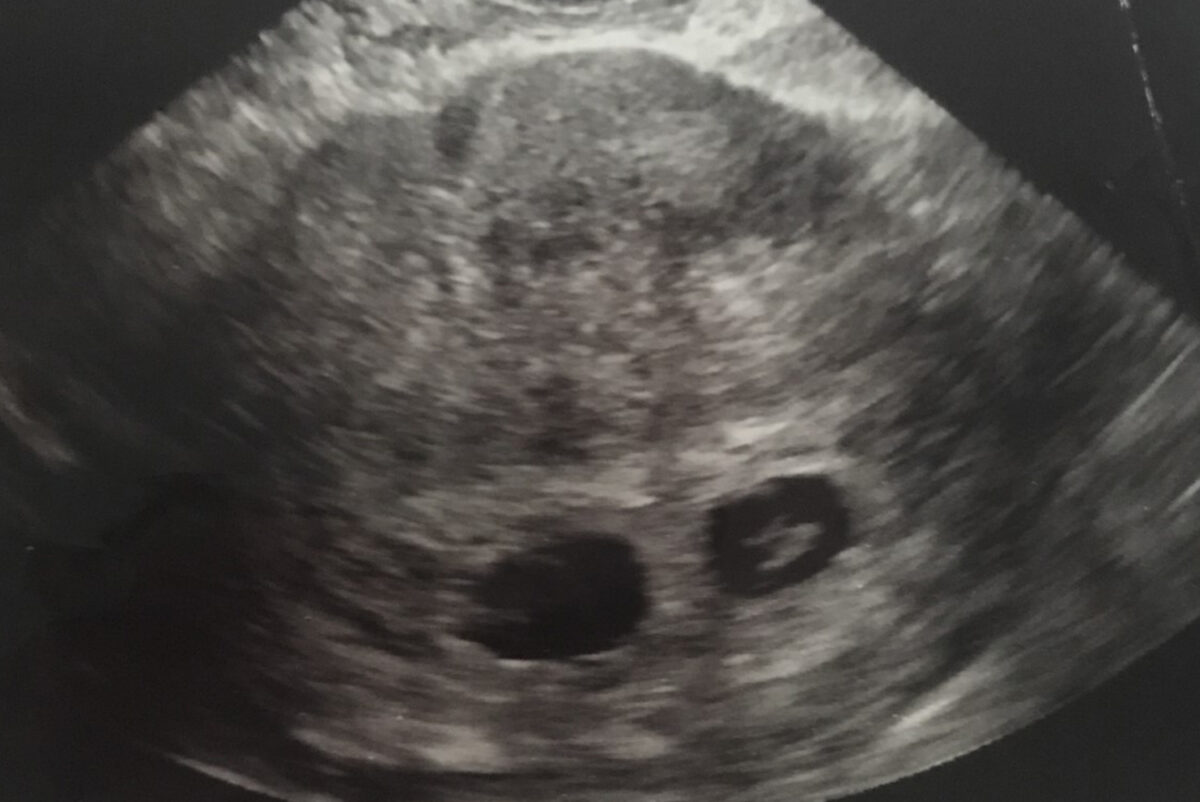

Lizeth Breaux, 37, from California, was 12 weeks pregnant with twins when medics discovered that one of them would be born with Down syndrome.